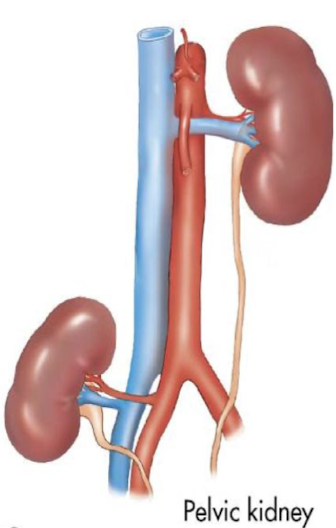

ectopic kidney

aka sacral kidney; adjacent to pelvis

??

ectopic (or sacral) kidney